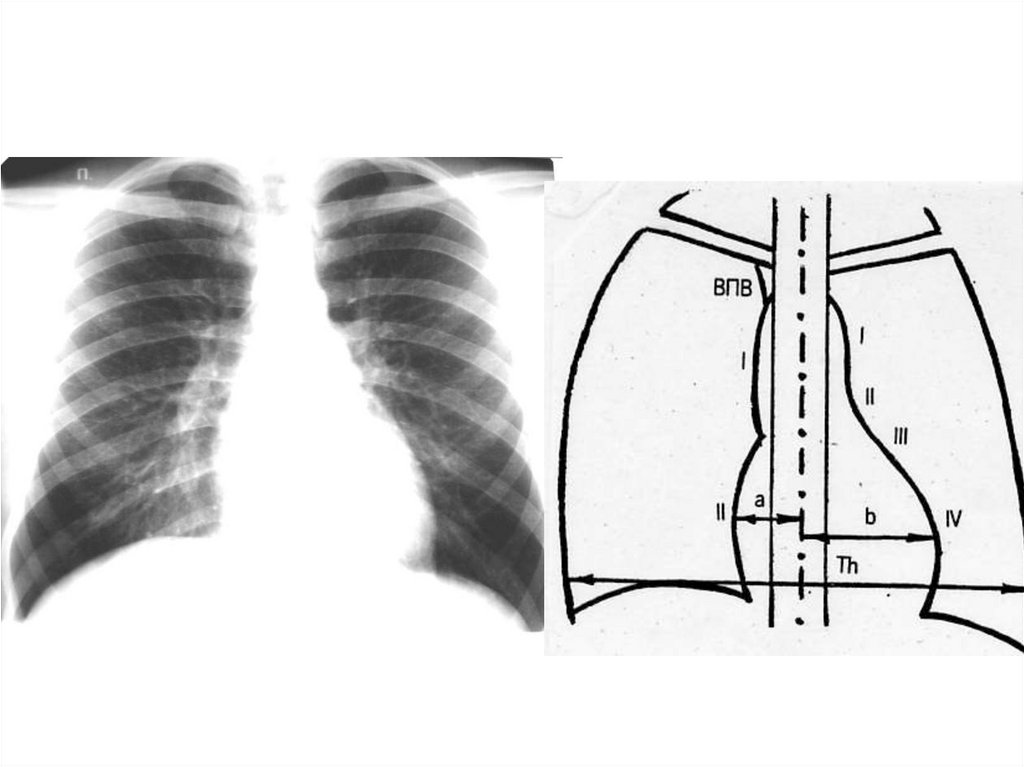

Лучевое исследование лёгких, сердца и крупных сосудов

Лучевое исследование лёгких,

сердца и крупных сосудов